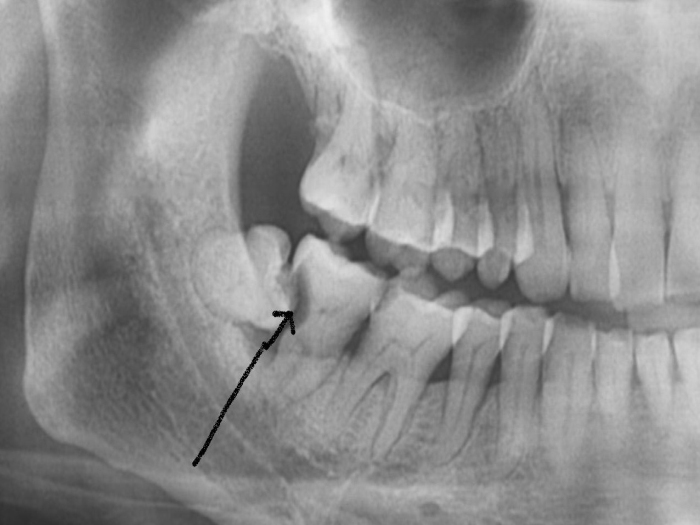

智齿在作怪。智齿是最容易塞的一颗牙了,因为大多数人智齿长得都不正,别的牙都是从下往上竖着长,可智齿经常从后往前横着长,于是它跟前面的牙之间就出现了一道楔形的沟,这样就极其容易塞牙。